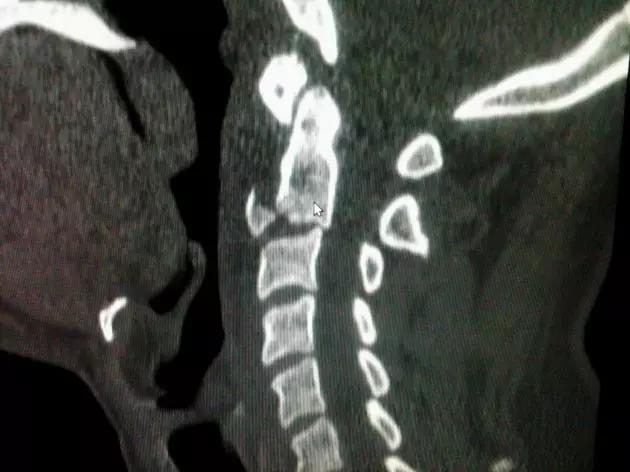

3. Chance 骨折

胸腰段椎体的分离性骨折,伴随脊髓、神经根、椎体的水平方向的崩裂骨折。又称座带骨折(seatbelt fracture)。

由 Chance 于 1948 年首先描述此骨折,故文献又常称 Chance 骨折,为一种屈曲拉伸骨折。典型的损伤机制为汽车座带束于患者腰腹部,当高速行驶的汽车突然减速或撞车时,座带支点以上的躯干屈曲,前冲力还同时产生一个向前拉伸的力量。将椎体由后方向前撕裂,骨折线横过椎体、椎弓根和椎板,椎体后部的韧带完全撕裂。有时前纵韧带亦可撕裂,常合并有神经系统的症状。

(来源:Radiopaedia)